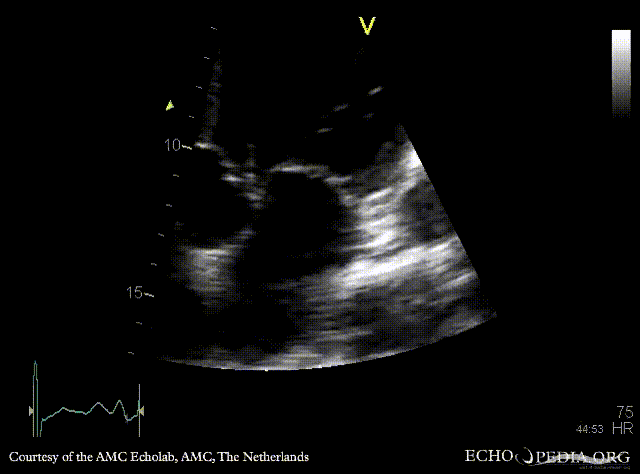

Severe aortic regurgitation

PLAX: aortic valve vegetation, dilated left ventricle PLAX: aortic valve vegetation